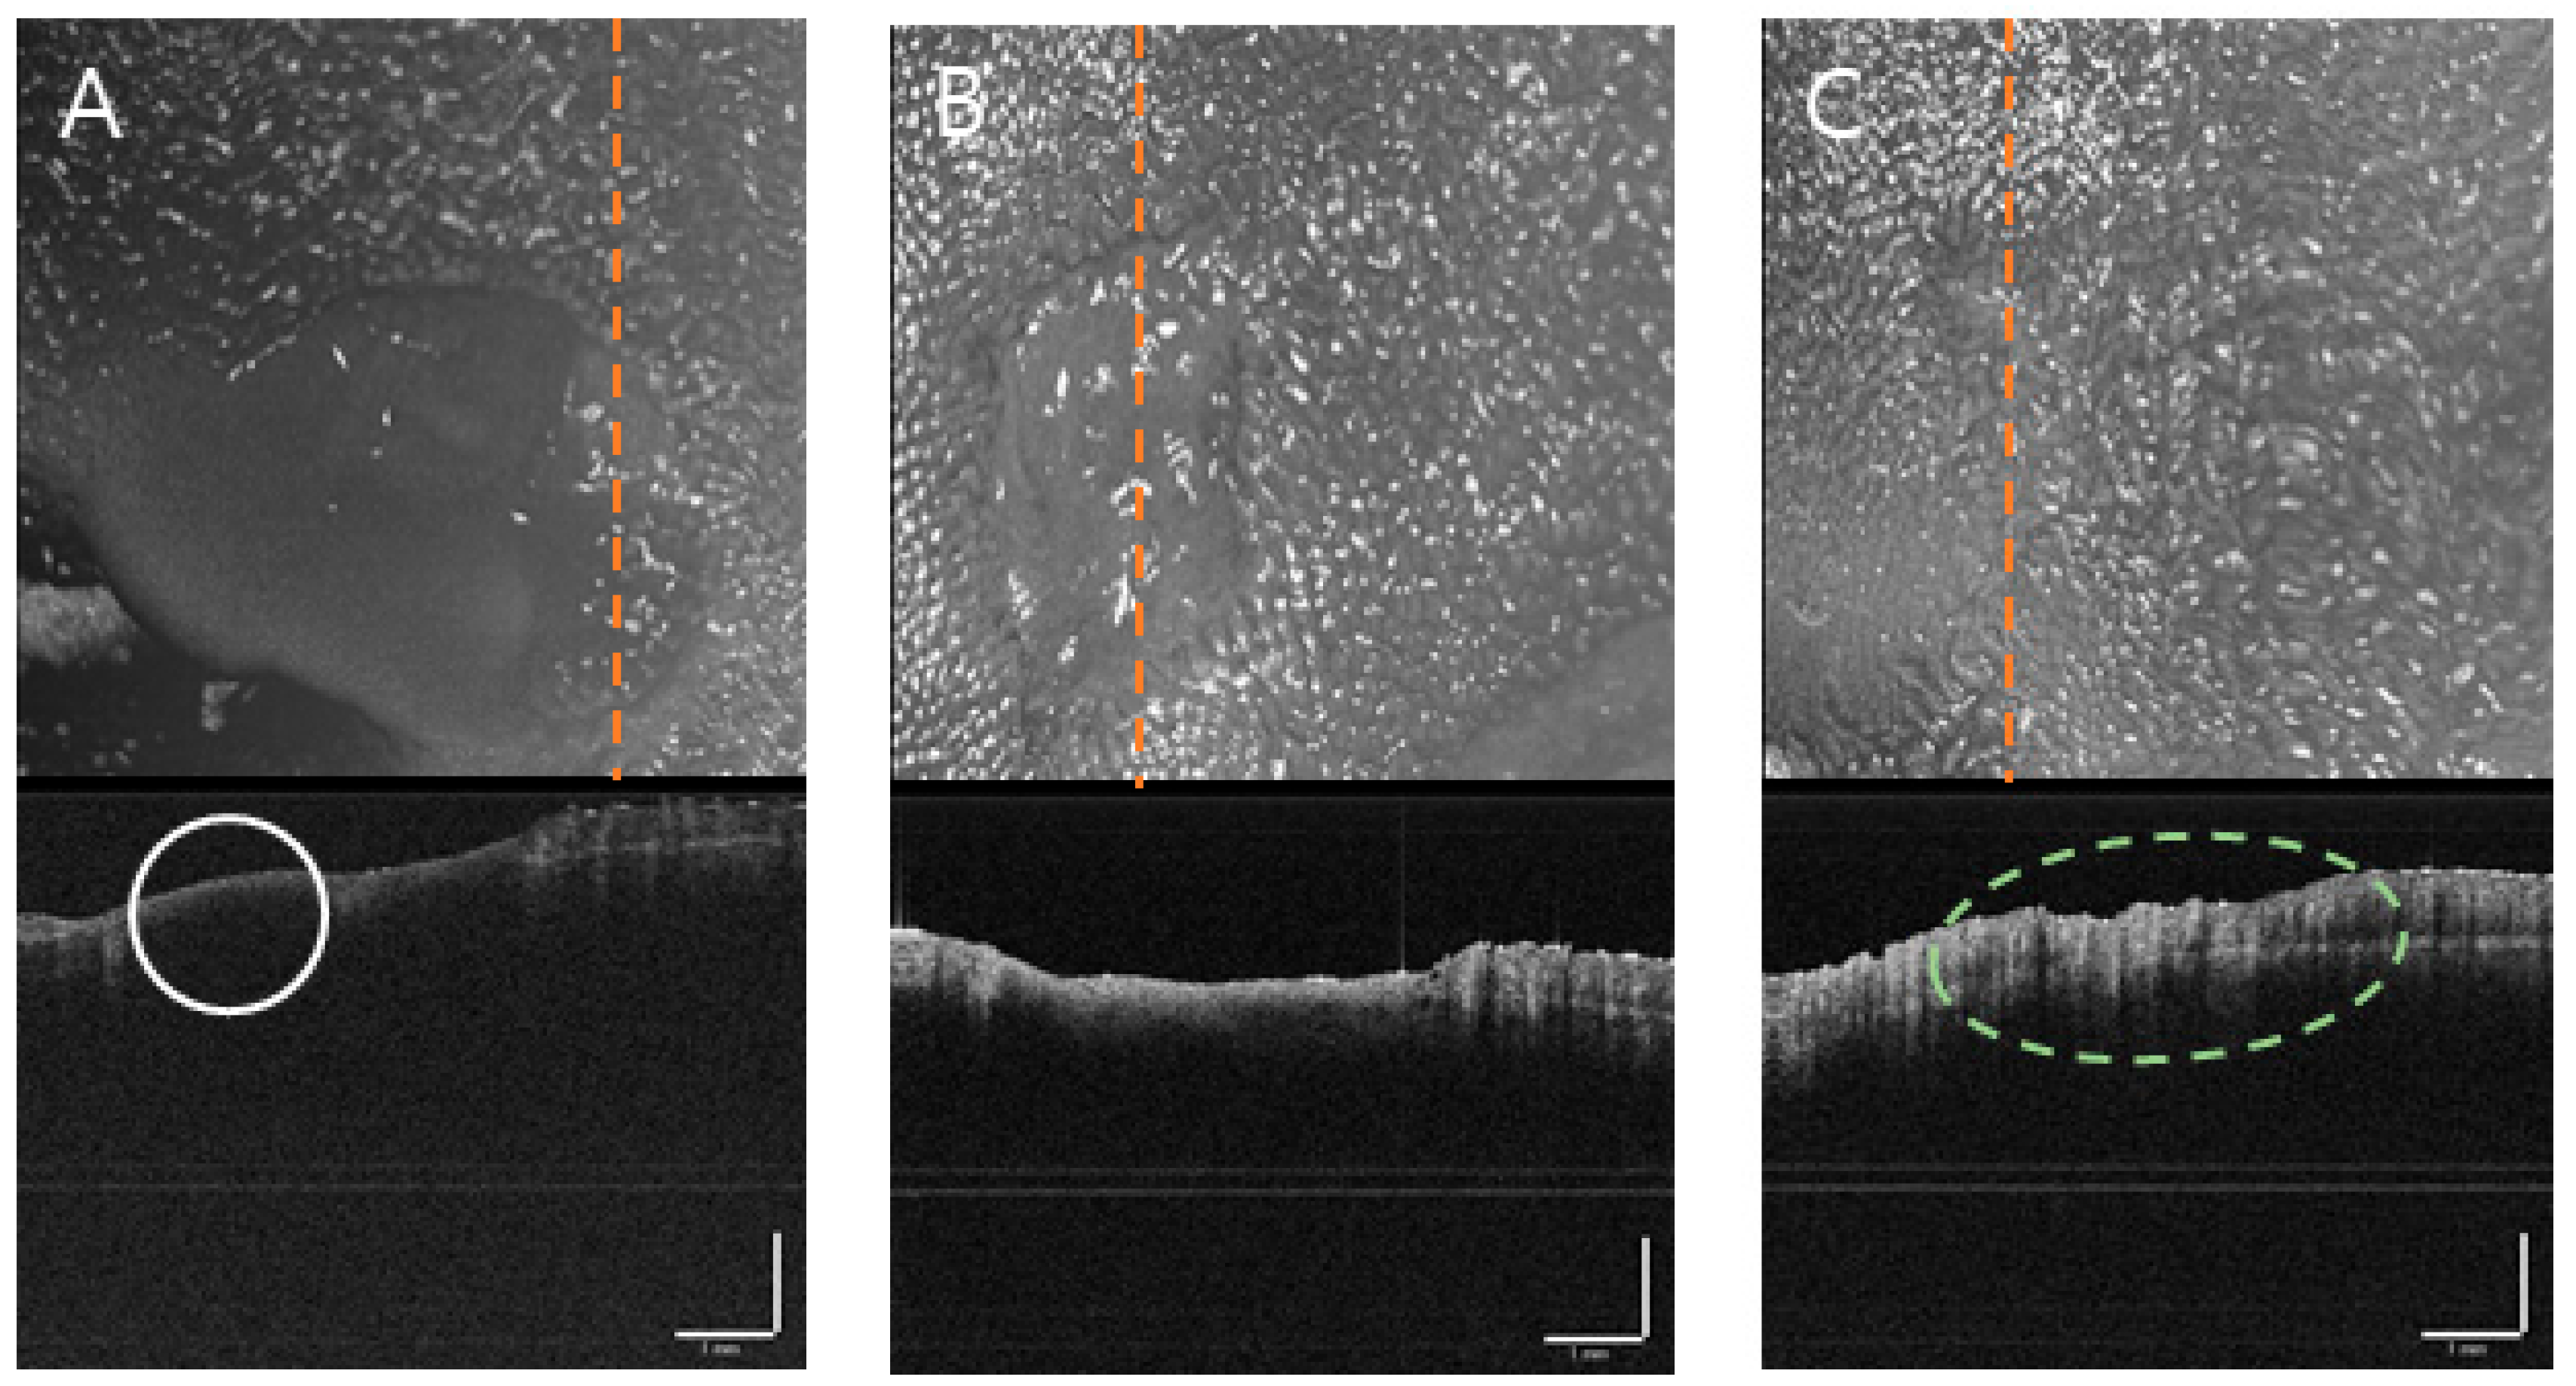

3.3.2. Tongue Ulcer

Laser

Tissue Punch